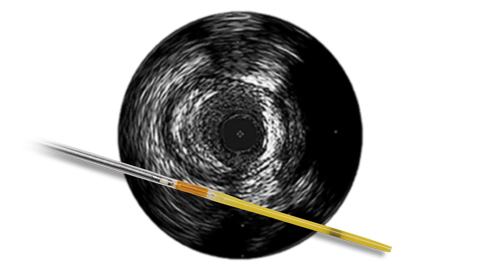

Ангиография дает сведения о характеристиках просвета сосуда, но не позволяет получить четкого изображения сосуда и поражения.

Между тем, использование ВСУЗИ помогает получить более четкую картину и улучшить результаты лечения пациента за счет планирования стентирования на основе данных и оптимизации стента после его установки1.